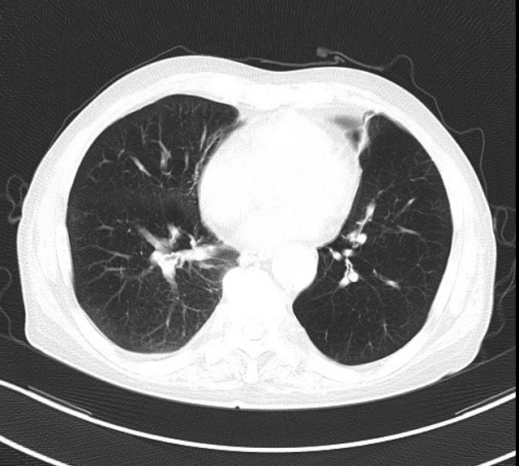

治疗前

治疗后

度过急性危险期后,治疗进入关键阶段——转呼吸内科进行后续专科康复。呼吸内科团队接过“接力棒”,制定个性化方案:无创呼吸机辅助、气道管理、肺康复训练、精准抗感染治疗。在医护人员的精心照护下,患者肺功能逐步改善,最终成功脱离呼吸机。